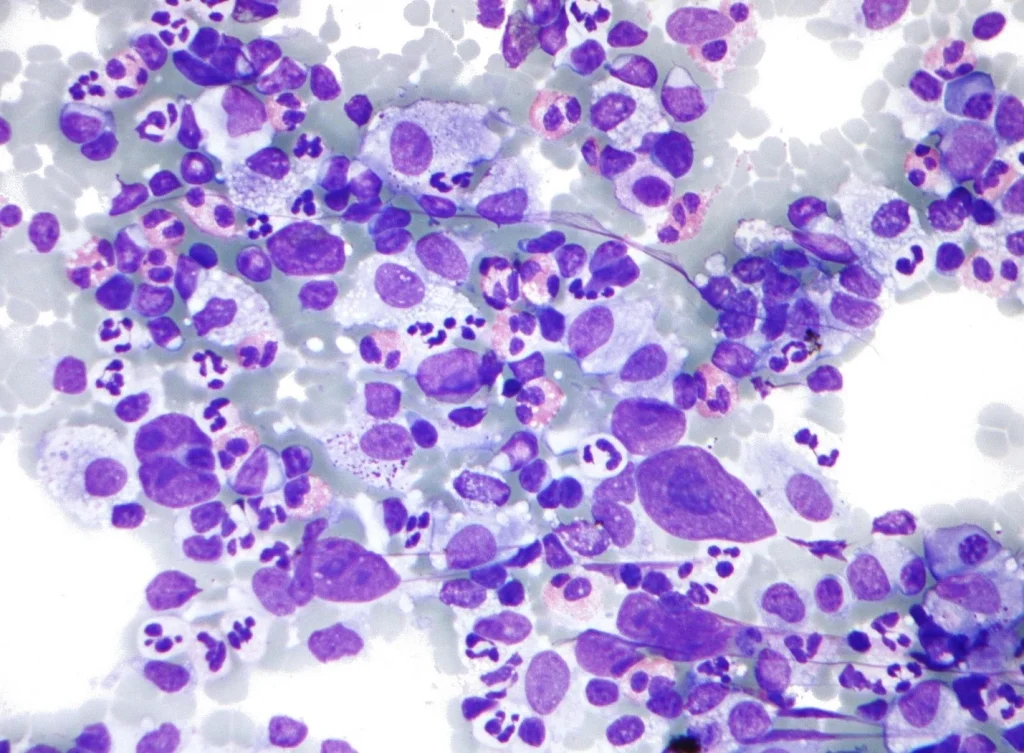

سلولهای سرطانی موجود در لنفوم هوچکین کلاسیک سلولهای رید-استرنبرگ (Reed-Sternberg cells) نامیده میشوند. این سلولها معمولا یک نوع غیر طبیعی از لنفوسیت B هستند. بزرگ شدن غدد لنفاوی در افراد مبتلا به لنفوم هوچکین کلاسیک معمولاً دارای تعداد کمی سلول Reed-Sternberg با تعداد زیادی سلول ایمنی طبیعی در اطراف آنها است. این سلولهای ایمنی دیگر باعث ایجاد بیشتر تورم در غدد لنفاوی میشوند.

لنفوم هوچکین غالب با لنفوسیت ندولار (NLPHL) حدود 5 درصد موارد را تشکیل میدهد. سلولهای سرطانی موجود در NLPHL سلولهای بزرگی به نام سلولهای پاپ کورن (popcorn cells) هستند (چون شبیه پاپ کورن هستند) که انواعی از سلولهای رید-استرنبرگ هستند. همچنین ممکن است این سلولها را با نام سلولهای لنفوسیتی و هیستیوسیتی (L&H) نیز بشنوید.

برخی از محققان فکر میکنند که عفونت با ویروس اپشتین بار (Epstein-Barr virus) گاهی اوقات باعث تغییرات DNA در لنفوسیتهای B میشود. در برخی موارد، این منجر به رشد سلولهای Reed-Sternberg میشود که سلولهای سرطانی در لنفوم هوچکین هستند.

دانشمندان تغییرات ژنی بسیاری را در سلولهای رید استرنبرگ یافته اند که به رشد و تقسیم سلولها کمک میکند یا باعث میشوند بیشتر از آن چه باید عمر کنند. سلولهای رید استرنبرگ نیز موادی به نام سایتوکاین (cytokines) میسازند که بسیاری از سلولهای دیگر را به غدد لنفاوی جذب کرده و باعث تورم (بزرگ شدن) آن میشود. به نوبه خود، این سلولهای غیر سرطانی موادی را آزاد میکنند که به رشد سلولهای رید-استرنبرگ کمک میکند.

تستهای آزمایشگاهی نمونههای بیوپسی

تمام نمونههای بیوپسی توسط یک پاتولوژیست (پزشکی که مخصوصاً برای تشخیص سلولهای سرطانی آموزش دیده است) زیر میکروسکوپ بررسی میشود که به دنبال سلولهای لنفوم هوچکین (به نام سلولهای رید-استرنبرگ) میگردد. گاهی اوقات اولین بیوپسی پاسخ روشنی نمیدهد و بیوپسیهای بیشتری مورد نیاز است.

نگاه کردن به نمونههای بافت زیر میکروسکوپ اغلب برای تشخیص HL (و نوع آن) کافی است اما گاهی اوقات به تستهای آزمایشگاهی بیشتری نیاز است.

ایمونوهیستوشیمی (Immunohistochemistry): این تست آزمایشگاهی پروتئینهای خاصی مانند CD15 و CD30 را روی سلولها جستجو میکند. اینها در سطح سلولهای رید-استرنبرگ در لنفوم هوچکین کلاسیک (cHL) یافت میشوند. آزمایشهای سایر پروتئینها ممکن است به لنفوم هوچکین (NLPHL) با لنفوسیت ندولر، به لنفوم غیر هوچکین (به جای لنفوم هوچکین) یا شاید به بیماریهای دیگر اشاره کند.